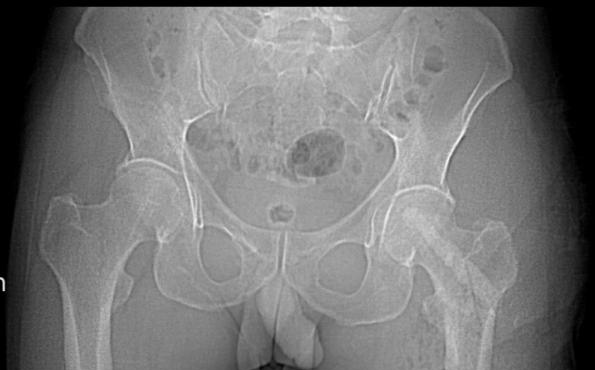

王先生几个月前出现左侧髋关节疼痛,遂到医院就诊,完善核磁共振检查,结果显示:左侧股骨头坏死。王先生习惯性上网一查,满屏「换关节」的信息让他寝食难安。怀着忐忑心情,王先生来到桂林医科大学第一附属医院关节与运动医学科就诊。陈椿荣副主任医师详细问诊、体格检查,并结合王先生先前磁共振检查结果,明确告诉王先生:「您的股骨头属于早期坏死,还有机会通过微创手术保髋治疗,无须置换关节!」这番话彻底打消了王先生的疑虑。

邹国耀主任对王先生的病情进行了详细评估,并组织科室医疗团队开展病例讨论。根据王先生情况,制定了髋关节镜下滑膜清理+髓芯减压死骨刮除后植骨+生物陶瓷棒置入的保髋手术治疗方案:

正常的股骨头表面光滑成球状,血供丰富;坏死的股骨头内部空洞、塌陷变形。然而,早期(ARCO I-II 期)发现时,股骨头通常尚未塌陷,此时是保髋治疗的黄金窗口。